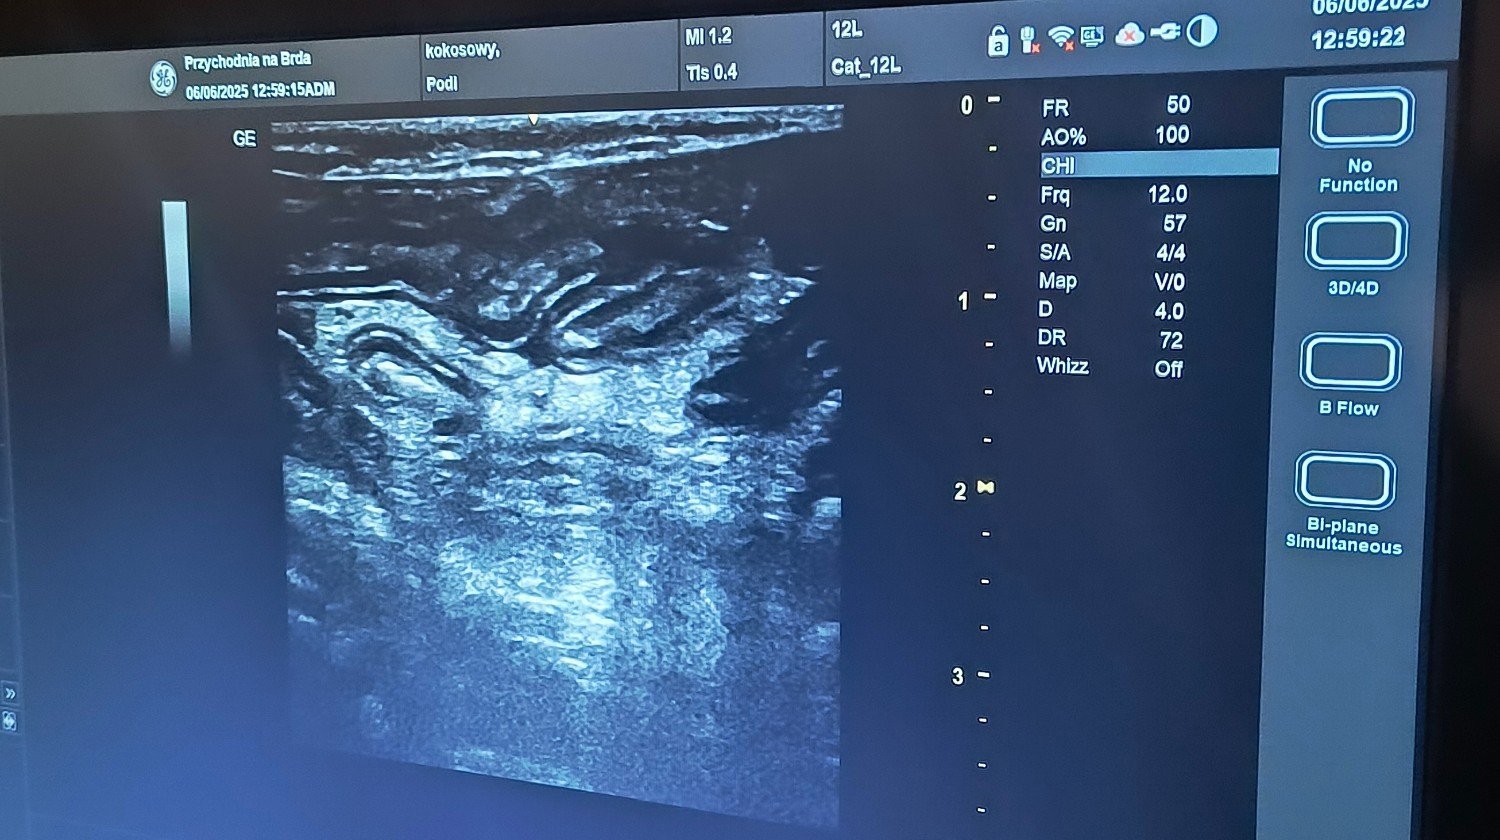

Jednak wczoraj wróciła gorączka i apatia. Podi straciła apetyt. 😭Dziś pobraliśmy krew i pojawił się płyn w brzuszku. Niestety leczenie kotki będzie kosztowne, 💸bo przecież nie pozwolimy jej odejść. Prosimy 🙏bardzo o pomoc w walce o koteczkę. Ona ma około roku i całe życie przed sobą.🥰